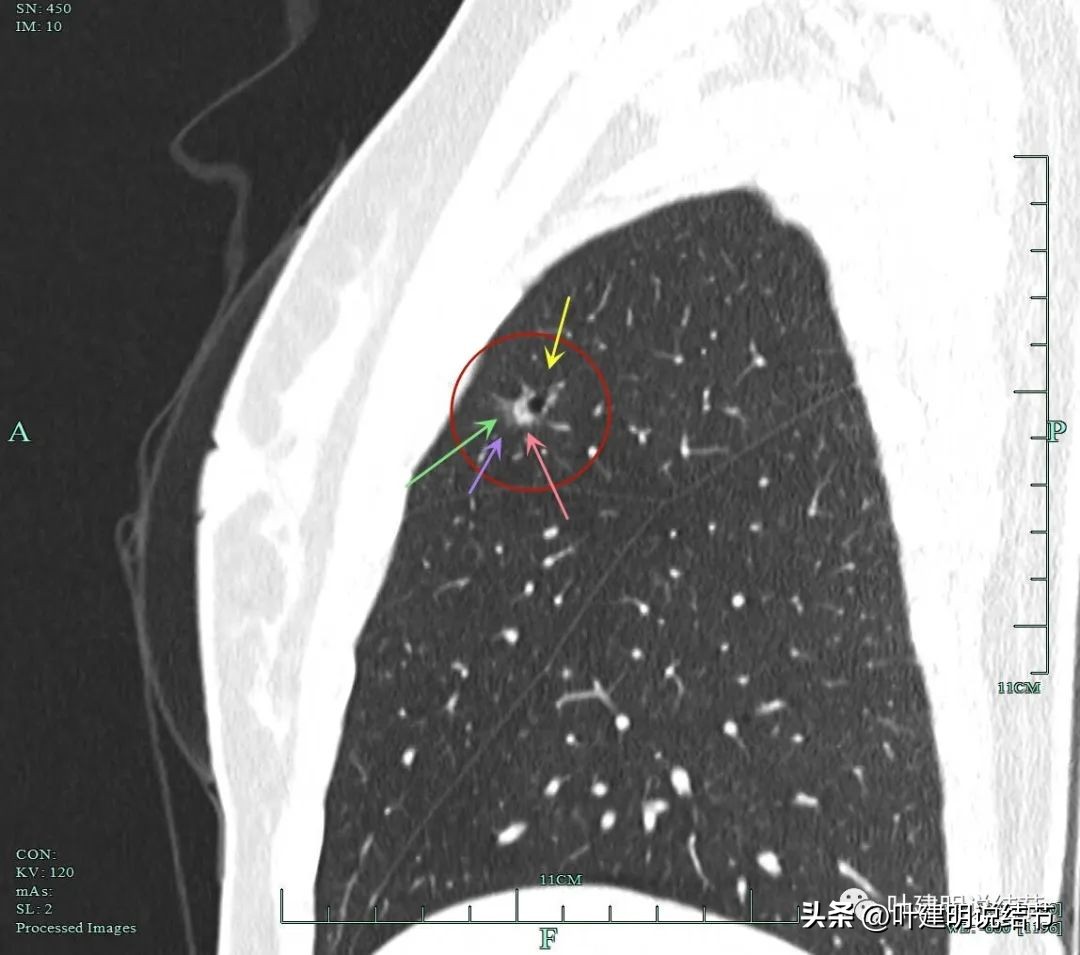

黄色箭头示病灶处有空腔征;粉色箭头示病灶内有实性成分;紫色箭头示毛刺征;绿色箭头示磨玻璃成分轮廓清,有毛刺。